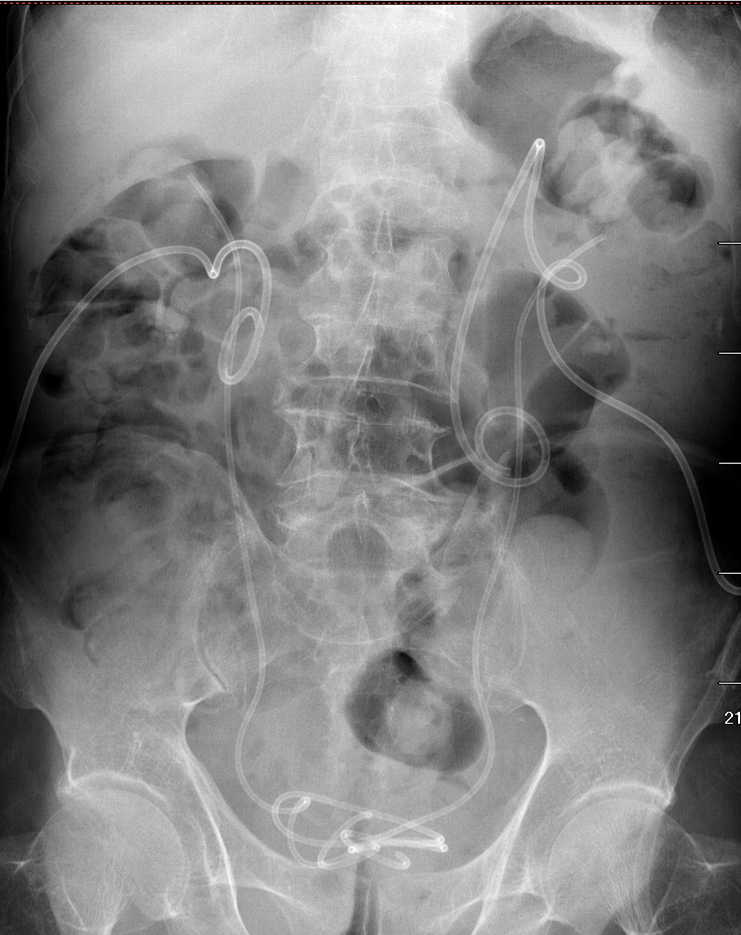

KUB提示右输尿管下段结石呈石街样排列,引起右输尿管完全梗阻,导致右肾萎缩

2016年04月手术患者,女性,32岁,昆山人,五年前曾因右输尿管结石引起肾绞痛于当地消炎补液解痉排石处理,疼痛缓解后未于重视,其间从未予复查,2周前出现右腰痛,与当地诊所就诊后予以震波碎石无效,并出现发热,急诊来我院就诊,CT:右肾萎缩,右侧肾脏积水,右侧输尿管多发结石形成石街约4.5*1.5cm,GFR:右侧17.2ml/min,左侧43.2ml/min。因左侧健肾代偿,肾功能正常:Cr 132umol/L;术前诊断:右输尿管下段多发结石 右肾萎缩 肾功能不全,鉴于右输尿管结石梗阻时间太长,肾功能不全,已处于失代偿期,最终也只能行右侧输尿管下段切开取术,解除输尿管下段梗阻,尽可能保护已经萎缩的肾脏,该患者预后不良。